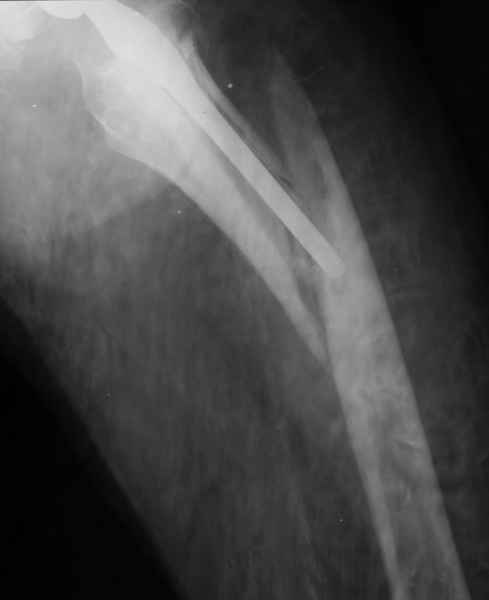

Весь проксимальный отдел бедренной кости ведь смещен относительно ножки эндопротеза? Значит менять ножку нужно. К тому же, если думать об удлинении ножки стержнем, место стыка получится как раз в области поперечной части перелома и о стабильности такой конструкции вряд ли можно будет думать. Так что - длинная ревизионная ножка с остеосинтезом. Может быть и серкляжей будет достаточно если перелом проксимальной части не оскольчатый (по снимкам не очень понятно).

ножка просела немного (вопрос, много - это сколько?)перечисленные проблемы - не самое важное сейчас, на них можно закрыть глаза. Ножка явно нестабильна, проксимальный отломок с б/вертелом к гвоздю не прицепить, срастется ли он с ножкой

Начинать, на мой взгляд, надо с того, что перелом-то произошел из-за порочной (варусной) позиции ножки, не случись он сейчас, это произошло бы еще через полгода при более невинных обстоятельствах. Не видел конструкций , но дизайн ножки сильно напоминает цементную стандартную ножку Мюллера и, стало быть, наверное есть цементная мантия. В любом случае, на реинтеграцию этой ножки расчитывать нельзя. Поэтому, если нет общесоматических противопоказаний, нужно выполнять ревизионное эндопротезирование, оптимальный вариант - ножка Wagner Cone.

Это"Corail", так что никакой цементной мантии там нет.Непонятно с чего Вы решили,что ножка была установлена в "варусе"? Нынешнее ее положение, получено после травмы.

Частично правильный ответ - 1. Это В-2 перелом (проксимальный отдел скорее жив, чем мертв). Костная пластика кортикальными трансплантатами необходима. Также необходим остеосинтез большим количеством проволочных металлических серкляжей. Пластина не нужна.

Используя ножку "Вагнер", как советует Рашид Муртазалиевич получите хорошую фиксацию по каналу, качественную адаптацию отломков, экономию финансов.